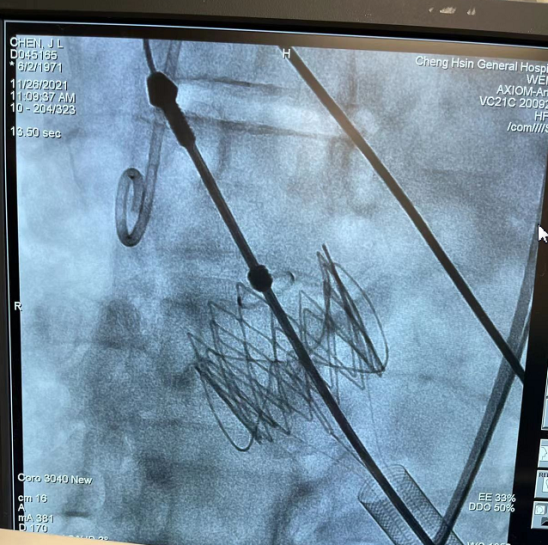

释放瓣膜后,瓣膜位置和形态理想

造影确认无反流和瓣周漏